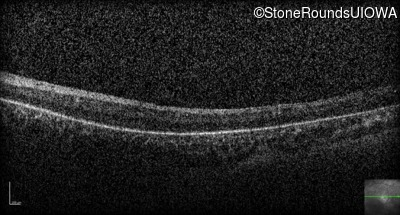

Optical Coherence Tomography - Right - Light Perception

Exemplar / OCT Stack

OCT Stack